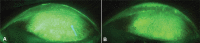

Purpose: Variability in the use of ophthalmic dyes to diagnose lid wiper epitheliopathy (LWE) has led to division in the literature and clinical practice. The principal aim of this study was to evaluate whether the use of a non-optimal methodology to identify LWE had a potential for false negatives; in which LWE was overlooked.

Patients and methods: A total of 20 participants were initially categorized to not have LWE and were enrolled in this study. The protocol examined whether or not LWE would later be revealed through the use of optimized methodology. Semi-automated analysis was performed of images taken after two different drop instillations with varying post-dye viewing times for both lissamine green (LG) and sodium fluorescein (NaFl).

Results: There was a significant increase in area of staining revealed when an optimal methodology for LWE identification was used. Comparisons for every non-optimal condition were statistically significantly different against the optimal condition (all p<0.01). The use of a non-optimal methodology resulted in a 70% false-negative rate when using LG and a 95% false-negative rate when using NaFl.